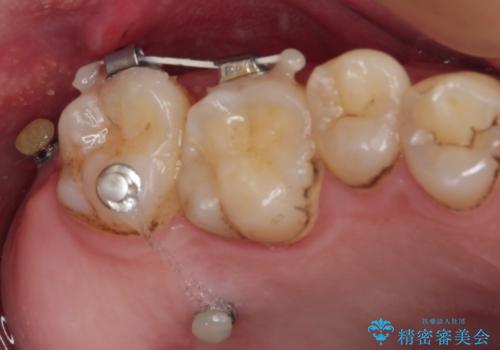

- 左下欠損部のインプラント治療を希望して来院された患者様です。

左下の欠損部を長期間欠損を放置していたことで、咬み合う上の奥歯が動いてしまっていたので、まずは上顎奥歯の部分矯正を行うこととしました。

理想的な咬み合わせに改善した上で、インプラント補綴治療を行うこととしました。

部分矯正を行ったこと治療期間は長くなりましたが、違和感のない咬み合わせを達成することができました。